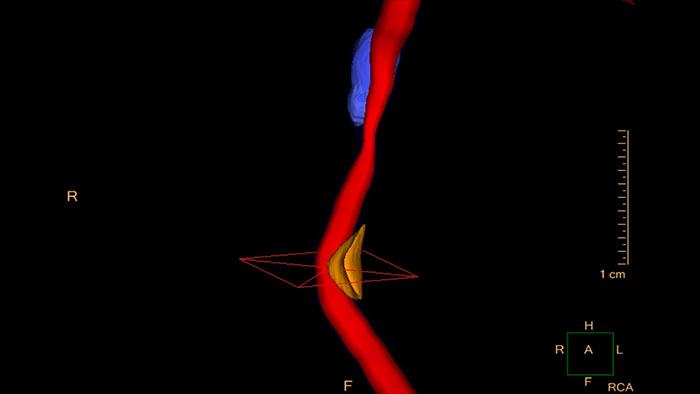

Cardiac Plaque Assessment

CT Cardiac Plaque Assessment

Evaluate coronaries plaque

Enables performing cross-sectional measurements along the coronary arteries, and automatically calculates regional and global quantities of plaque volume.

Benefits

• Provides automatic color-coded visualization of plaque content areas on vessel cross-sectional images.

• The user has the ability to edit the automatic results.